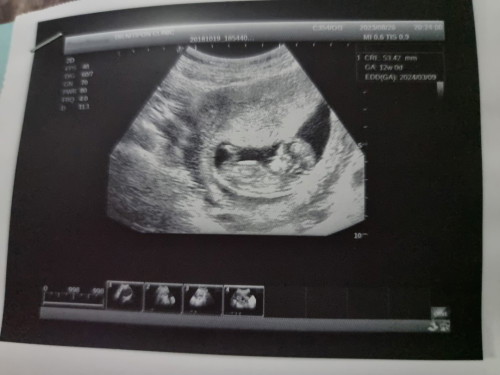

มีนาค่ะ...น้อง ผช👶